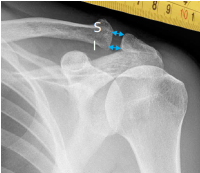

Q what is the name of this measurement? and what is the average + range?

A: Acromioclavicular Joint Space (A/C Joint Space)

assesses the joint space between the acromion and the clavicle. The average is 3.3 mm for males (range 2.5-4.1 mm) and 2.9 mm for females (range 2.1-3.7 mm).